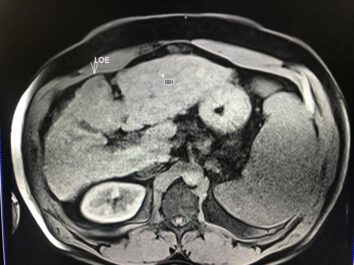

Masculino de 52 años, con cirrosis hepática. La elastografía ecográfica evidencia fibrosis Categoría F3 según escala de METAVIR y la presencia de múltiples nodulaciones, que en su mayoría son menores a 2 cm.

En este contexto, toda nodulación mayor de 1 cm, debe ser evaluada idealmente con RM trifásica con secuencia de Difusión , para discriminar si se trata de nódulos de regeneración , nódulos displásicos o hepatocarcinoma.

En el presente caso, encontramos una lesión típica de hepatocarcinoma en el segmento 5 ( hiperintensa en T2, restringe en la Difusión con ADC bajo. Realza heterogéneamente postcontraste EV, con wash out y presencia cápsula tardía).

El objetivo es identificar dentro de la multifocalidad de nódulos , un hepatocarcinoma precoz o de pequeño tamaño , cuando la posibilidad de tratamiento con intención curativa es viable , a pesar de la cirrosis.